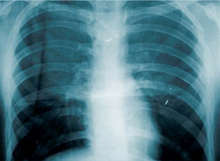

Fokus-og-handling-giver-mindre-sygdomSynkning af mundhulebakterier bliver i stigende grad kædet sammen med penunomi (lungebetændelse) som følgevirkning.